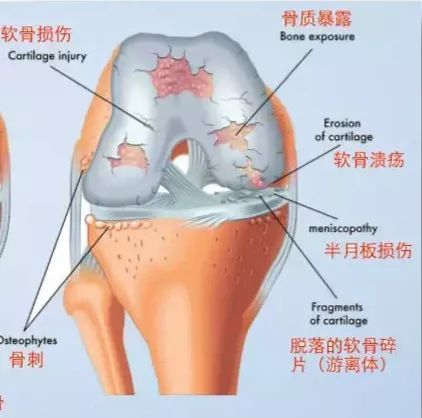

骨關節炎的病理表現為關節軟骨纖維化、皸裂、潰瘍、脫失。軟骨的破裂缺失,就導致關節疼痛及壓痛,疼痛在各個關節均可出現,其中以髖、膝及指間關節最為常見。初期為輕度或中度間斷性隱痛,休息后好轉,活動后加重。疼痛常與天氣變化有關,寒冷、潮濕環境均可加重疼痛;骨關節炎晚期可以出現持續性疼痛或夜間痛。此外,還會出現關節絞鎖、關節腫脹等癥狀。